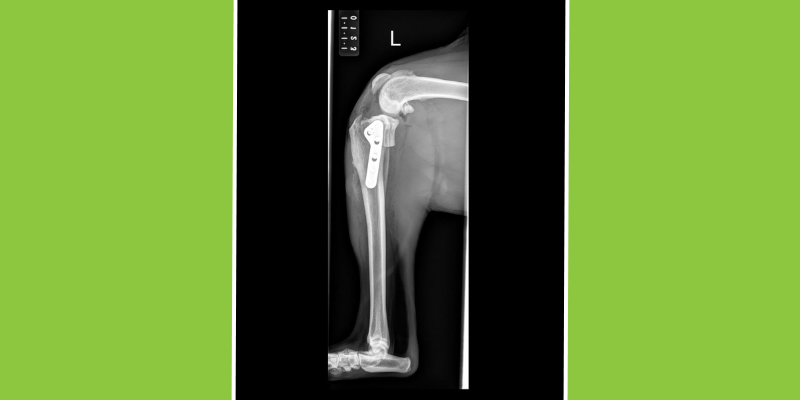

X-ray after a TPLO surgery.